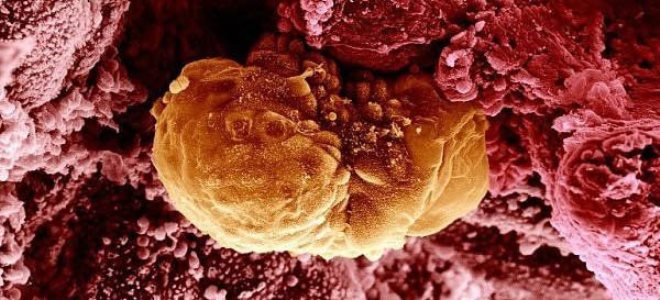

Медицина и диагностика: Инвазивный пузырный занос на УЗИ

Раздел: Альбом идей